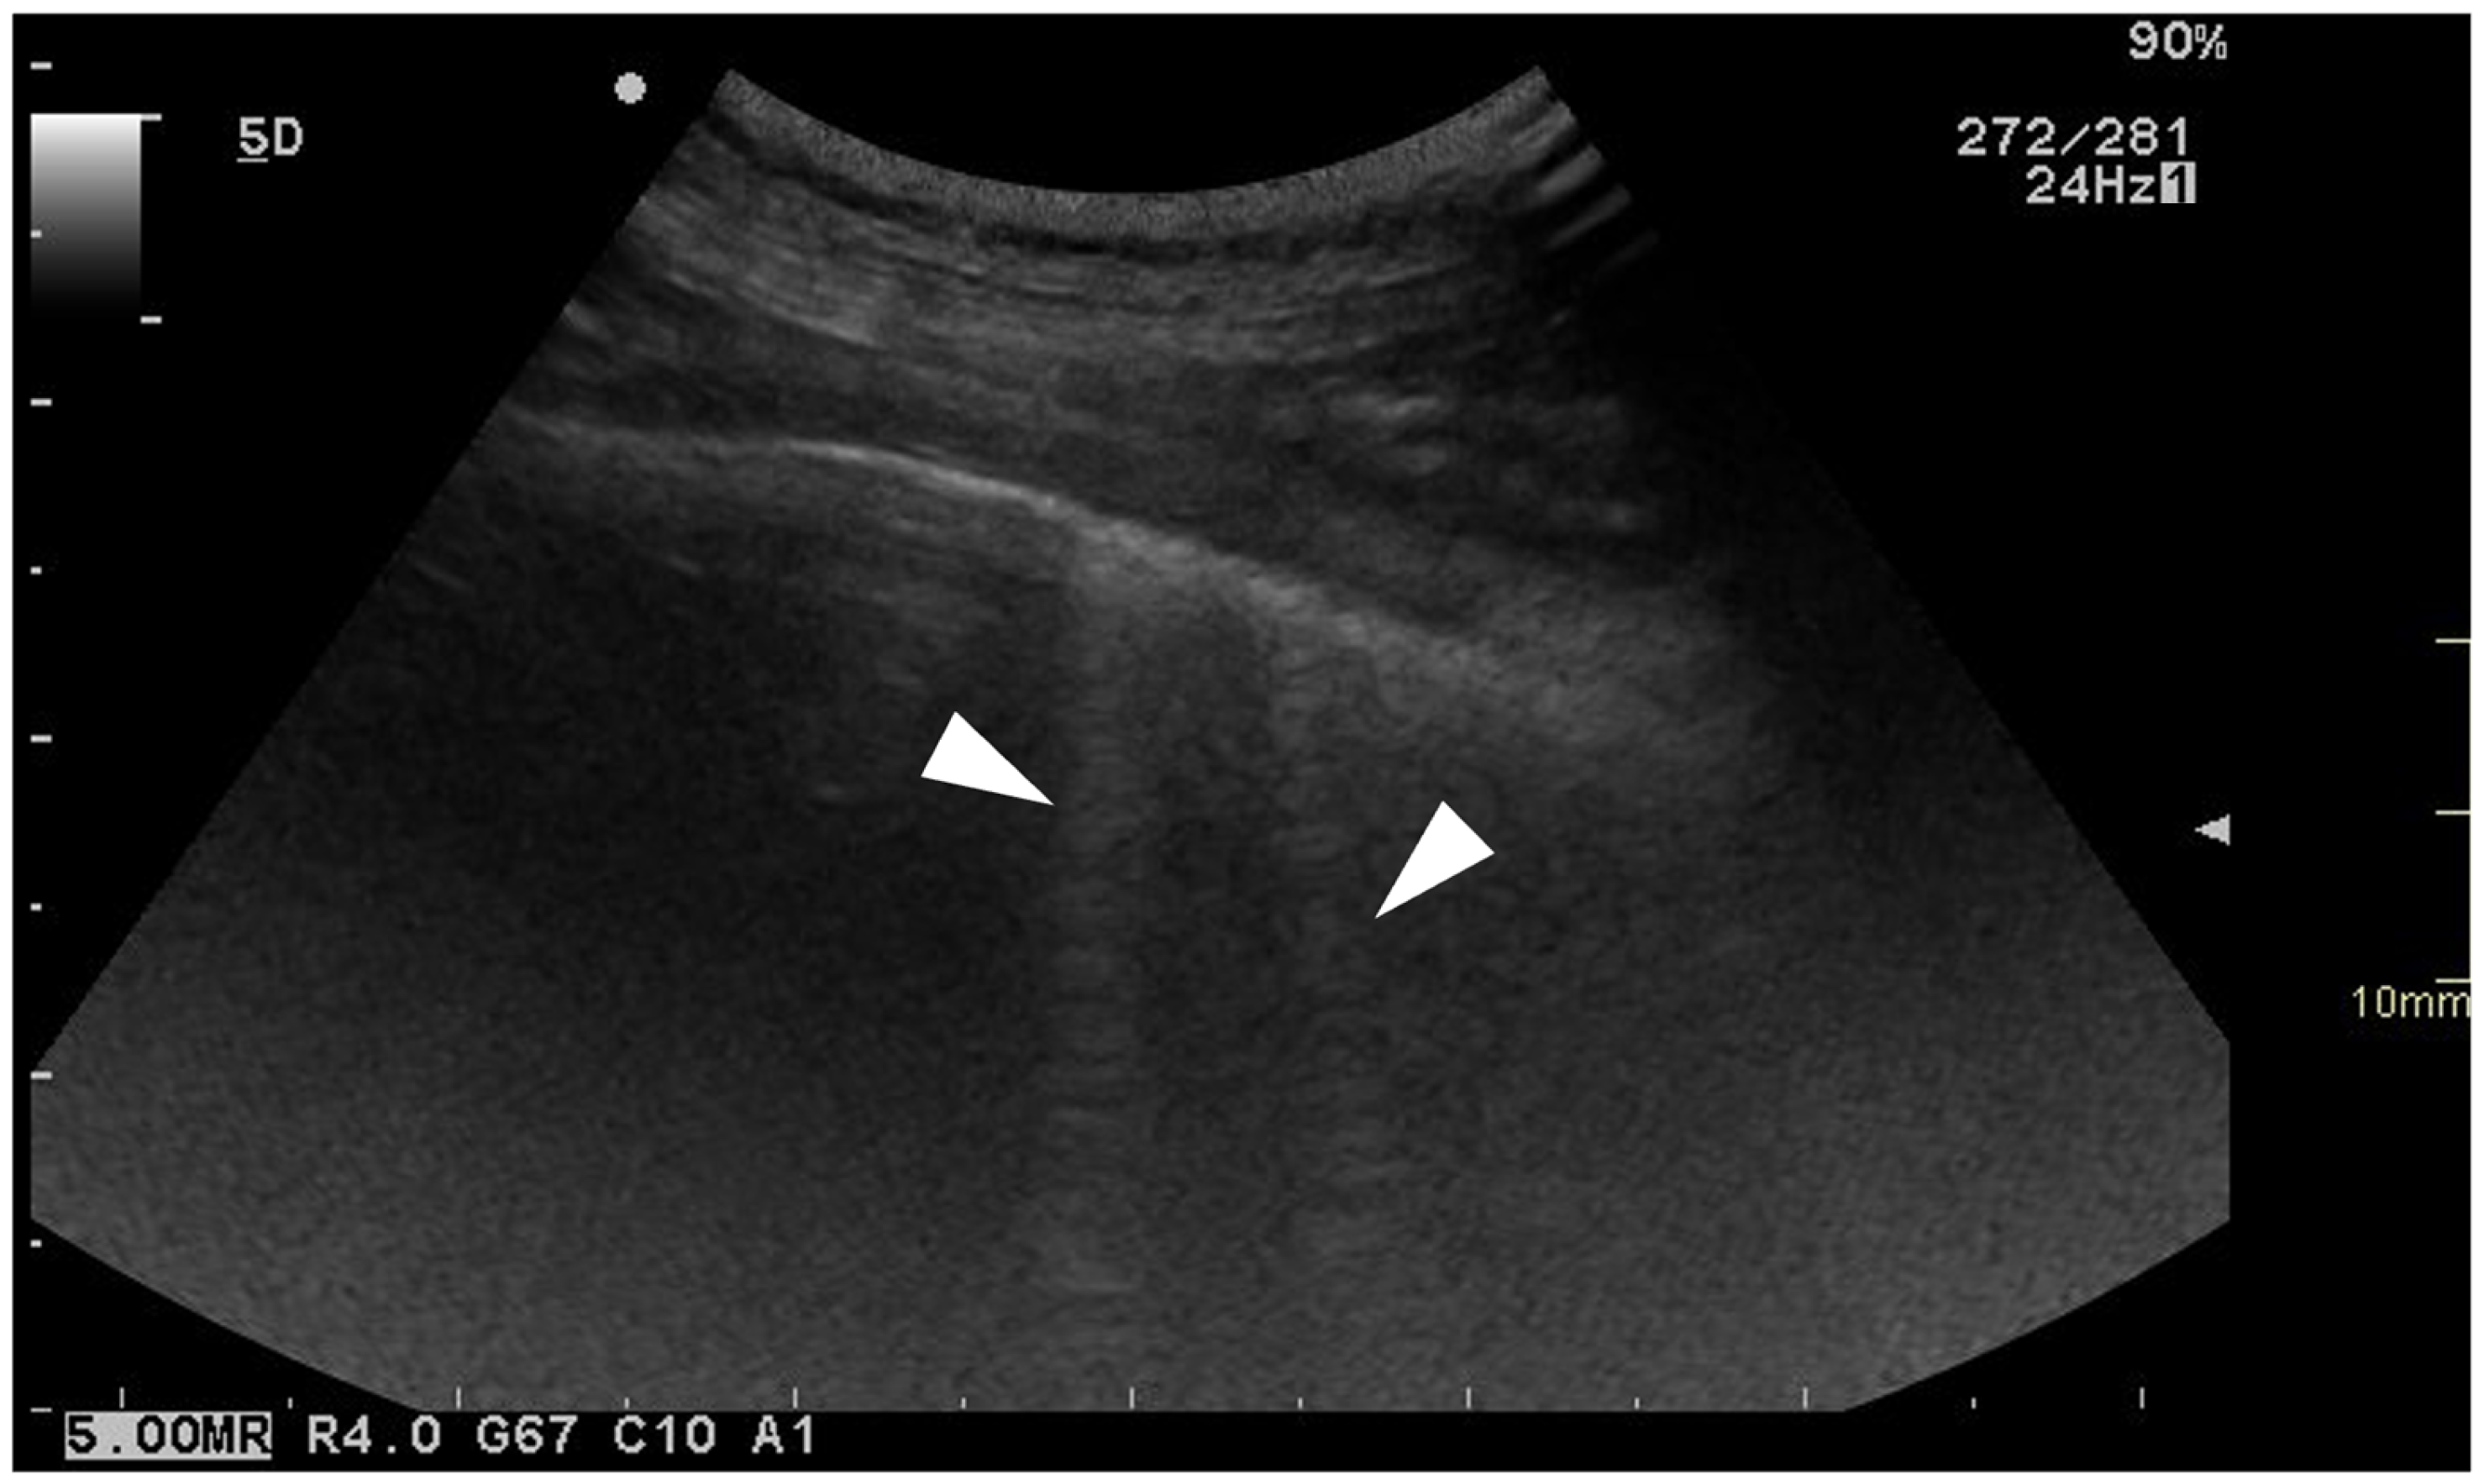

For each location, the presence and the number of ring-down artefacts (Figure 1) were counted. Depending on the number of artefacts, a score was obtained from 0 to 3 (Table 1). A similar method was applied for other lung lesions, such as peripheral hypoechoic pulmonary nodules or hypoechoic pulmonary areas (Table 1, Figure 2). The pleural surface was defined as smooth or irregular (Table 1, Figure 3)—scores of 0 or 1—and pleural sliding was assessed as present or absent (Table 1)—scores of 0 or 1. Pleural effusion was assessed as present or absent—scores 0 or 1 (Table 1). The scores were summed for each location and each side, and a total score out of 72 was attributed to each dog. Examinations were performed by the same operator (GB) on all dogs in a blinded fashion.

Figure 2. Ultrasonographic image of the thorax of a WHWT affected with CIPF showing a peripheral hypoechoic pulmonary nodule (white arrow). The image was obtained in a transverse orientation (parallel to the ribs).